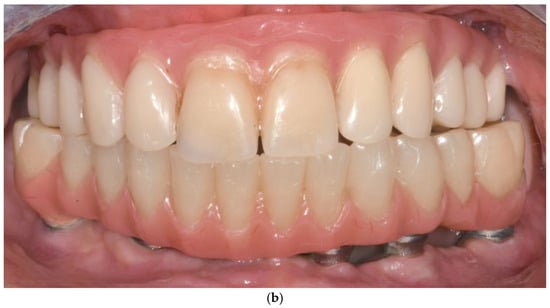

- Immediate loading with provisional prosthesis (24–72 h post-op). (Supports soft tissue healing and functional rehabilitation).

- Final prosthesis placement after 4 months. (Ensures tissue maturation and long-term durability).

- Passive fit and absence of considerable cantilevers. (Prevents biomechanical overload and prosthetic complications) [52].